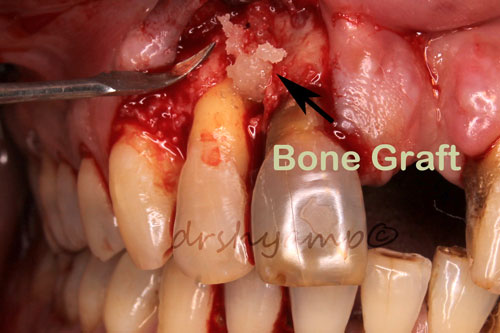

Periodontal flap surgery with bone grafting

Periodontal flap surgery with bone grafting

Periodontal flap surgery with bone grafting

Periodontal flap surgery with bone grafting

Periodontal flap surgery with bone grafting

Periodontal flap surgery with bone grafting

Periodontal flap surgery with bone grafting

Periodontal flap surgery with bone grafting

Periodontal flap surgery with bone grafting

Periodontal flap surgery with bone grafting

Periodontal flap surgery with bone grafting

Periodontal flap surgery with bone grafting

Periodontal flap surgery with bone grafting